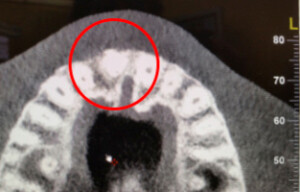

L’implant a été positionné dans l’alvéole, aligné avec la racine. À ce stade, un guide chirurgical peut s’avérer extrêmement utile, en particulier pour éviter d’éventuels obstacles anatomiques, tels que des paquets vasculo-nerveux situés dans le trou rétro-incisif.

L’implant dentaire peut être posé avant ou pendant la réalisation des greffes osseuses et gingivales, avec l’adjonction de PRP et de PRF. Une option consiste à utiliser une guidance numérique lors de la pose de l’implant. La fabrication d’une couronne céramique cosmétique fixe, qui reconstitue la couronne dentaire naturelle, intervient après l’ostéo-intégration de l’implant dentaire et la maturation des greffes.